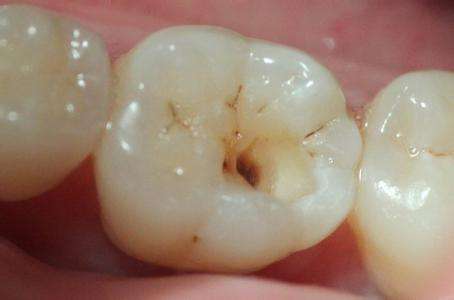

什么是龋齿 龋齿,俗称“虫牙”、“蛀牙”,它并不是虫子把牙齿蛀坏了,而是在以细菌为主的多种因素影响下,牙齿的牙釉质、牙本质或牙骨质发生的一种慢性、进行性、破坏性的疾病。龋齿... 补牙 吴芳芳 550 2023-11-15

补牙为什么越早越好 如果患了龋病就应尽可能地早修补,因为龋洞经过修补后可以阻止龋病病变的发展,及早恢复牙齿的功能,保持牙列的完整若不进行及时治疗,病变就会越来越大,从浅龋发展到深龋... 补牙 范姜英杰 569 2023-11-25